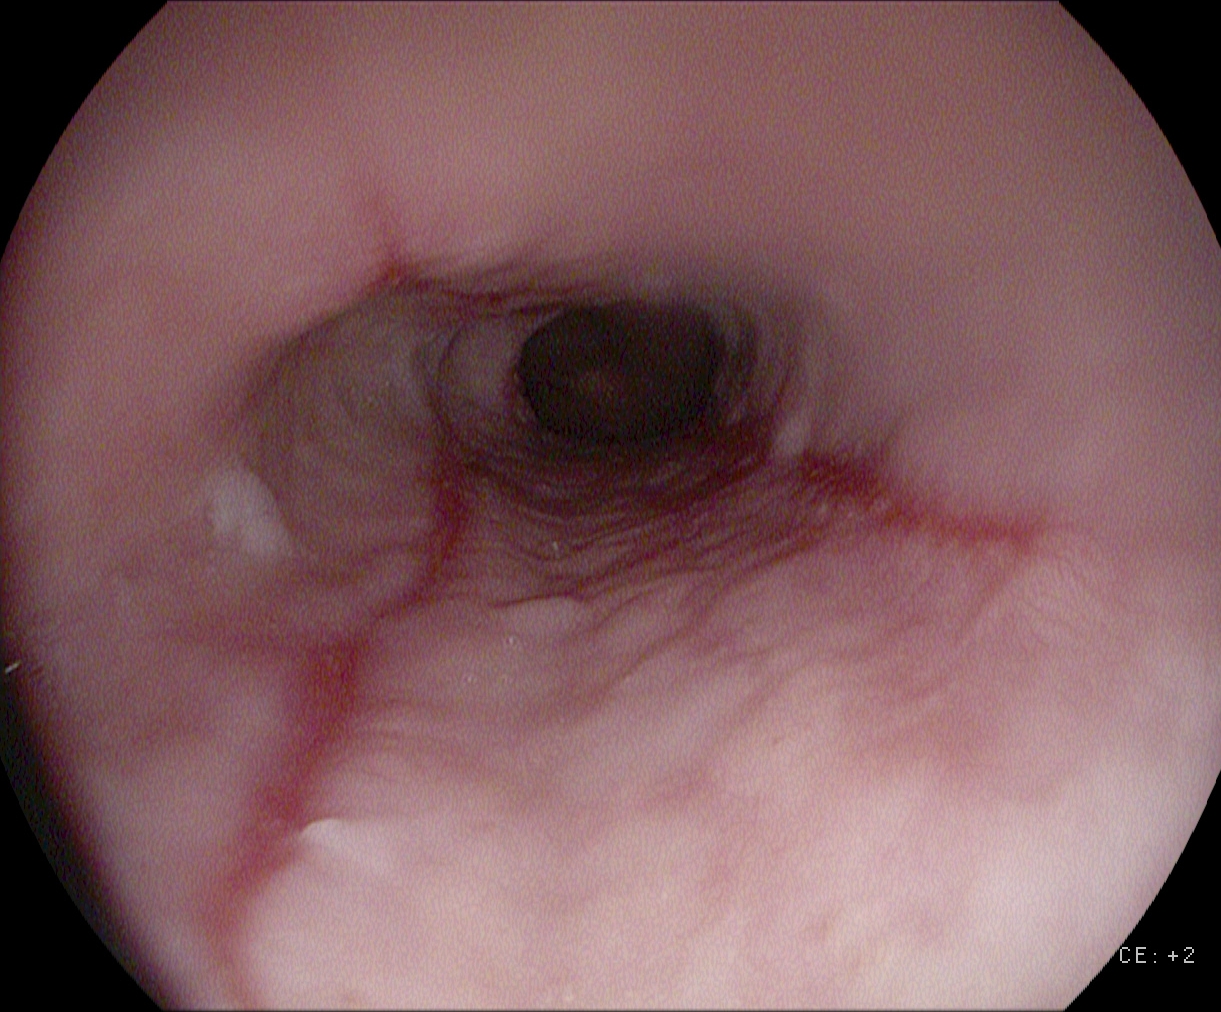

The Kvasir V1 is a datatset of GI-tract images annotated by the medical experts [22]. The dataset consists of 4000 labeled RGB images varying image size from 720×576720\times 576 to 1,920×1,0721,920\times 1,072 pixels. There are 8 classes of the images and each class consists of 500 labeled images. The classes of the images are anatomical landmarks including Z-line, pylorus and cecum, the pathological findings include esophagitis, polyps and ulcerative colitis and removal of polyps including the dyed and lifted polyp and the dyed resection margins.

Hyper Kvasir is a dataset of GI-tract images annotated by various medical domain experts [25]. The dataset consists of 110,800 GPEG images of the GI-Tract abnormalities varying sizes. The image dataset was divided into 10,662 labeled images (training) of 23 classes, 99,417 unlabeled images and 721 images for the test set. The image sizes are varying from 352×332352\times 332 to 1079×19201079\times 1920 with 3 channels. Some of the images from EndoTech 2020 are shown in the Fig. 4. The dataset is highly class imbalance with the minimum 6 images in class hemorrhoids and the maximum of 1148 images in class bbps-2-3. The classes are of five categories including anatomical landmarks, pathological and normal findings and endoscopic procedures.

Figure 4: Some images from Hyper Kvasir Dataset [25]